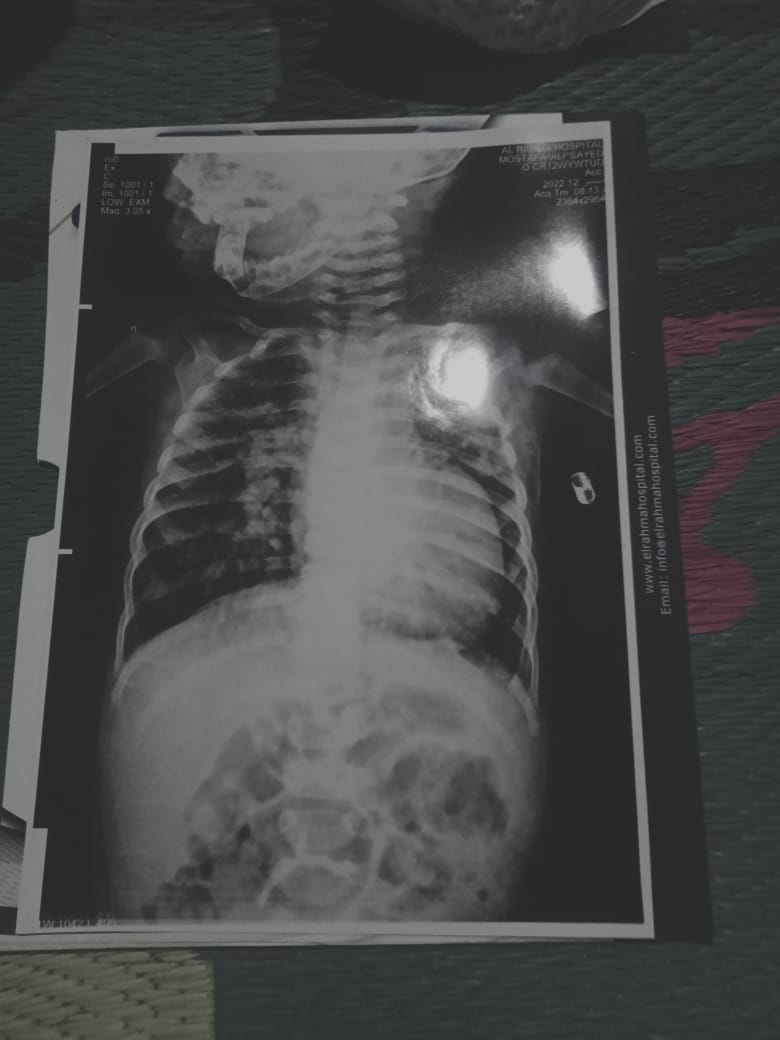

وأكد والد الطفل أن لديهم الأوراق وصور الأشعة والتحاليل والتقارير، التي يؤكد من خلالها الأطباء على إصابة الطفل مصطفى بثقب في القلب مع ضرورة العلاج.